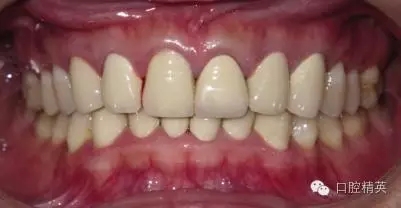

關(guān)于基礎(chǔ)治療。牙周治療和根管治療是美觀修復(fù)的基礎(chǔ)。根據(jù)術(shù)前檢查,常規(guī)先行全口潔治,必要時局部深層次的牙周治療,待牙周情況穩(wěn)定后,再考慮牙體預(yù)備與取模(見圖1、2)。在牙周炎未控制或牙齦紅腫的情況下,是不可能預(yù)備好牙齒,不可能取得清晰的印模,更談不上成功的美觀修復(fù)。

LAVA 全瓷冠強度高,顏色自然,邊緣高度密合,切端可見半透明感,整體效果理想,與修復(fù)前(見圖1)相比取得了醫(yī)患均滿意的效果。